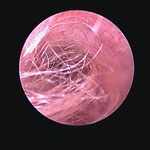

角化症、脂漏症という生まれつきの体質を持ったワンちゃんは耳垢が多くなりがちです。また、角化症、脂漏症の長毛種となれば、耳の中に毛が生えた犬種も多く耳道から耳垢を排泄しにくくなります。それらが原因で耳に汚れがたまります。また長毛種はトリミングに行く回数も多く、耳を洗う機会が多くなります。こんな負の連鎖があり、いずれも耳を悪くする大きな原因になります。その全ての要因に対処しなければ耳の病気は解決しません。写真は鼓膜手前に耳垢や毛が蓄積し、通常の耳洗浄ではきれいにできない状態です。セカンドオピニオンで来院されるワンちゃんで最も多い病気の1つです。

フレンチブルドックはアトピー性皮膚炎、食物アレルギー、脂漏症、甲状腺機能低下症など皮膚病になりやすい犬種です。さらにフレンチブルドックの耳道はもともと入口がとても広く、鼓膜手前で極端に狭くなっています。もし、これらの皮膚病を発症すると外耳炎が起こりやすくなります。外耳炎が起こると耳垢が溜まり、耳洗浄による耳道刺激があったり、微生物の増殖など負のサイクルに陥ることがあります。さらに耳道周囲の体毛が耳の中に入りやすいため、鼓膜手前に毛が蓄積します(写真)。体毛、微生物が増殖した耳垢、皮膚病の放置といった悪化因子が重なると非常に重度の中耳炎になります。